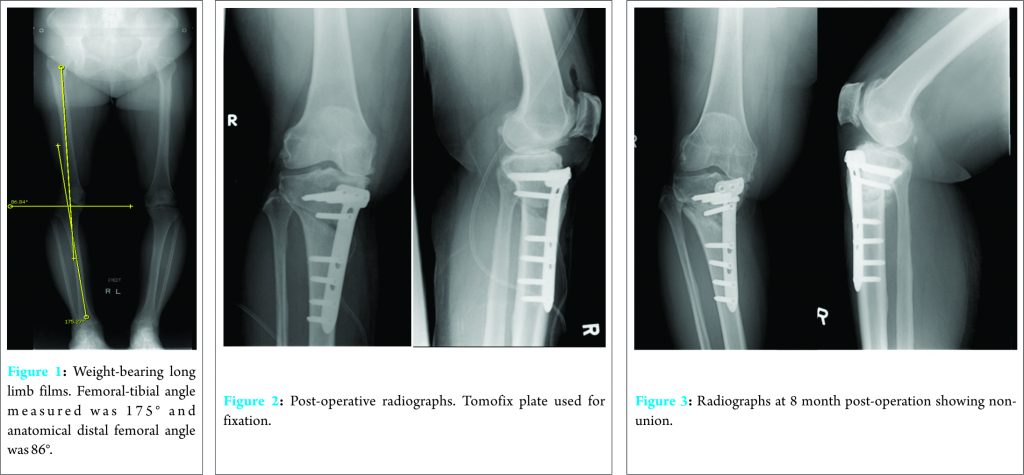

A 53-year-old Chinese lady, with a history of hypertension, diabetes mellitus and chronic depression, presented with an 8 month duration of severe medial right knee pain associated with varus knee deformity. Pain was exacerbated on walking and standing. She was initially treated conservatively with a course of non-steroidal inflammatory drugs, intra-articular visco-supplementation, physiotherapy and weight loss regime. Despite a two-year trial of non-surgical therapy, she continued to experience a deterioration in her symptoms with limitation of her functional status requiring a quadstick as a walking aid. Clinical examination revealed bilateral genu varum. Range of motion was limited to 0 to 110° with no fixed flexion deformity found bilaterally. Significantly, there was medial joint line tenderness and absence of lateral joint line and patellofemoral tenderness. Minimal effusion was found in the right knee. No limb length discrepancy or varus knee thrust was found. Bilateral weight-bearing knee and long limb radiographs were performed (Fig. 1). Significant medial compartment radiographic osteoarthritic changes were noted in the right knee, corresponding to Kellgren-Lawrence grade 3 osteoarthritis. These changes included loss of medial joint space, varus knee deformity and the presence of marginal osteophytes. The femoral-tibial angle measured was 175° and the anatomical lateral distal femoral angle was 86°. We performed a diagnostic knee arthroscopy and then proceeded to an opening wedge high tibial osteotomy using the Tomofix plate after a failed two year trial of conservative therapy (Fig. 2). Arthroscopic findings include medial compartment Outer bridge grade 4 lesion with degenerate radial tear of the posterior horn of the medial meniscus. The lateral compartment had no cartilage or meniscal tear. Intra-operative correction with the opening wedge osteotomy was guided with the use of radiographic imaging. Post-operatively, she was started on a rehabilitation programme, progressing to partial weight bearing at about 6 weeks.

However, she continued to experience pain over the osteotomy site up till 6 months post-operatively. Pain was exacerbated on standing and ambulation. Repeat radiographs showed minimal callus formation over previous osteotomy site (Fig. 3). She was treated conservatively with continued protected weight bearing. However, her symptoms deteriorated and she developed a fix flexion deformity of her right knee. A computed tomogram performed 8 month post-operatively revealed non-union of the osteotomy site with hardware failure and loss of correction (Fig. 4). Three proximal screws were broken and 1 screw had back-out. The proximal tibia was angulated laterally in varus and anteriorly increasing the tibial plateau slope. Inflammatory markers were not elevated.

The patient subsequently underwent revision plating with autologous bone graft. The surgical approach was similar to the index surgery. Intra-operatively, findings were consistent with CT scan results. The screws were completely removed together with the Tomofix plate. Bone edges were freshened and the alignment was corrected under radiographic imaging guidance. Autologous cancellous iliac crest bone grafts were harvested and compacted into the osteotomy site. A proximal tibial locking plate was placed on the posteromedial aspect and locking screws were used to secure the fixation. The previous plate was medial. Intraoperative cultures sent were negative for infection. Post-operatively, the patient progressed from non-weight bearing to partial weight bearing at 3 months and full weight-bearing at 6 months post-operatively. She no longer experienced pain at the osteotomy site and repeat radiographs performed at 1 year post-operatively showed union (Fig. 5). She was able to ambulate without any walking aids and no longer has any limitations in her daily activities.